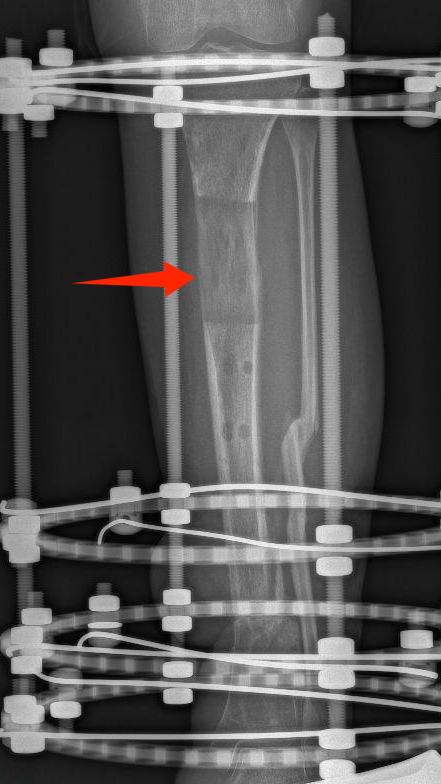

多年来,贵州航天医院各科室紧跟医学前沿,不断强技术、补短板,大力开展新技术、新项目,完成了许多高精尖、高难度、本地区“首例”的技术,填补了医院医疗技术空白,满足了群众日益增长的医疗需求。 贵州航天医院骨科率先在遵义地区开展骨搬移技术,截至目前,已治愈慢性骨髓炎、感染性骨不连、骨缺损、脉管炎、糖尿病足患者200余例,糖尿病足治疗保肢率达到98%。 本期,我们将为大家带来骨科特色技术——骨搬移技术(Ilizarov)。 案例分享 一名59岁的患者,身患糖尿病12年,在来我院3个月前出现了右脚溃烂的症状,来院就诊时,患者的右脚十分红肿,右脚脚趾坏死,伤口处不断流出黑红色脓液,情况十分严重。在接诊到患者时,骨科专家团队高度重视,立刻为患者完善了CT血管造影(CTA)等相关检查,诊断为:2型糖尿病,糖尿病周围血管病变,右糖尿病足。 术 前 考虑到患者情况比较严重,为最大限度保证患者肢体完整,科室专家团队进行了严格的讨论评估,为患者制定了骨搬移技术治疗方案,在征得患者及其家属的同意后,成功通过搬移骨块为患者进行治疗,促进患者病变肢体血管再生。 胫骨横向骨搬移外架固定 清除感染病灶 术后调节外架,通过搬移骨块 促进患肢血管再生 患者在术后三周前来换药,观察到感染得到进一步控制;术后六周复查,患者病变处已愈合,进行CT血管造影(CTA)后可明显观察到足部血管再生。 术后3周 术后6周愈合 CT血管造影见足部血管再生 糖尿病患者全身与局部的问题互为影响,形成恶性循环,糖尿病足溃疡创面迁延不愈,常见干性坏疽、湿性坏疽、趾坏死、深且大的溃疡以及骨髓炎等症状,还可导致脓毒血症,以往为保全生命,患者被迫选择一次或多次截肢。骨搬移技术的发展进步,能在血糖有效控制、局部有效清创下,有效促进患肢微血管再生,改善患肢血供,达到糖尿病足更快治疗康复的目的,并能根据病变情况最大限度的保障患者肢体完整。 什么是骨搬移技术 骨搬移技术是通过使用专用的骨外固定器固定骨段,每天缓慢牵拉,在牵拉搬移过程中,骨段尾部形成新骨及新的软组织,从而修复骨骼缺损及软组织缺损。是治疗大段骨缺损、骨不连、骨感染、肢体畸形的金标准方法,也用于治疗脉管炎、糖尿病足等肢体缺血性疾病。 骨感染缺损 切除感染段 搬移骨段 新骨形成 骨感染根治愈合 骨搬移技术原理 生物组织在持续、稳定、缓慢牵拉下,能刺激细胞分裂、组织再生,骨外固定技术运用该原理,通过持续缓慢调节外固定器形成牵拉张力,促进牵引成骨与相邻组织再生,如神经、血管、肌肉、皮肤等再生,达到治疗大段骨缺损、肢体缺血如糖尿病足等疾病的目的。 骨搬移技术优势 (一)除治疗骨缺损、骨不连外,有更广的适用范围,利用组织再生、血管再生等特性,能大量运用于肢体畸形的矫形、糖尿病足等的治疗。 (二)治疗效果确切,重建肢体外型和功能,极大降低截肢率和残疾率。 (三)明显提高了患者生活质量,极大减轻其家庭及社会负担。 肢体畸形的矫形 慢性骨髓炎 骨段切除 术后1年 濒临截肢的脉管炎术后6周 难愈创面术后3周 贵州航天医院骨科 专家团队 赵学平 骨科主任 主任医师 临床擅长:从事骨科临床工作30余年,对骨科常见疾病的诊治具有丰富的临床经验。 世界中医药联合会脊柱康复专业委员会常务理事,中华中医药学会整脊分会常务委员,中国中西医结合学会骨伤科分会肢体矫形功能重建与康复专家委员会常务委员,中国研究性医院学会骨科创新与转换专业委员会关节外科学组保髋工作委员会常委,中国康复技术转化及发展促进会骨外科与康复技术转化专业委员会常务委员,泛珠三角区域运动医学联盟(PPRD-SMA)理事会常务理事,中国研究型医院学会运动医学专业委员会委员,贵州省中医药学会整脊分会副主任委员,贵州省中西医结合学会银质针专业委员会副主任委员,贵州省康复医学会骨与关节专业委员会常务委员,贵州省人民医院骨科专科联盟常务理事,贵州省康复医学会骨内科专业委员会常务委员,中华医学会贵州省骨科学会委员,贵州省康复医学会脊柱脊髓专业委员会常务委员,贵州省运动医学分会委员,贵州省康复医学会骨与软组织肿瘤专业委员会委员,遵义市医学会创伤分会副主任委员,贵州省康复医学会骨内科专业委员会遵义地区分会常务委员,遵义市医疗事故鉴定、伤残鉴定、工伤鉴定、司法鉴定专家。 长期从事骨科临床研究及教学工作,在国家级、省部级杂志发表论文20余篇,SCI论文2篇,参与主编骨科专著2部,主持省部级科研项目2项,参与指导省部级、市级科研项目6项。 陈明勇 骨科副主任 副主任医师 临床擅长:从事创伤骨科工作约20年,对骨缺损、骨不连、骨肿瘤、肢体畸形等的肢体矫形重建及功能重建,慢性化脓性骨髓炎的根治治疗、糖尿病足的保肢治疗、快速康复理念(ERAS)下的老年骨折的诊治,四肢复杂骨折的诊治,四肢骨折等微创手术治疗具有丰富的临床经验。 2004年毕业于遵义医学院临床专业,曾在中国人民解放军总医院、广西医科大学第一附属医院、上海第六人民医院骨科进修。中国中西医结合学会骨伤科专业委员会横向骨搬移治疗糖尿病足及微血管网再生学组首届委员,遵义市医学会创伤分会常务委员。 瞿 辉 骨科 副主任医师 临床擅长:对骨科的常见病、关节外科、脊柱外科及运动医学疾病的诊治具有丰富的临床经验,熟练掌握骨科手术操作技术。 毕业于遵义医学院临床医学系,2005年前往广州中山大学第一附院骨显微医学部进修学习,2011年前往成都华西医院进修学习,并多次在省内外学习骨科相关知识,是中华医学会骨科分会会员。 赵兴东 骨科 主任医师 临床擅长:擅长骨科的常见病及各种创伤、四肢骨折创伤修复、骨感染、手足疾病的诊治和手足体表畸形的矫形整复,熟练掌握骨科四肢骨病及创伤的手术操作技术,尤其在四肢关节复杂性损伤、手足外伤、组织缺损创面、难治创面的皮瓣修复方面及平足、高弓足矫形方面及四肢慢性疼痛诊治、康复方面具有丰富的临床经验。 硕士研究生,毕业于遵义医学院临床外科系,2015年前往山东省立医院手足外科进修学习;遵义市医学分会创伤分会第一、二届委员,遵义市手外科医学会第二委届员会常务委员;在省级及省级以上期刊发表文章9篇,参编著作2部,参与主持并完成市级课题1项,参与市级课题2项、省级课题1项。 张俊凯 骨科 副主任医师 临床擅长:从事骨科临床工作28年,对创伤骨折、骨感染、骨缺损、骨不连等外科诊治,四肢骨折的微创手术治疗,四肢复杂骨折(如关节内粉碎性骨折、多发骨折等)的损伤控制及手术治疗等具有丰富的临床经验。 1995年毕业于遵义医学院临床专业,2009年前往复旦大学附属医院骨科进修1年。 卢懿明 骨科 副主任医师 临床擅长:从事骨科工作18年,对创伤骨折、四肢骨折的微创手术治疗、四肢复杂骨折(如关节内粉碎性骨折、多发骨折等)的损伤控制及手术治疗,尤其是髋部骨折的PFNA等微创技术,踝关节骨折、膝关节周围骨折的Mipo微创技术等具有丰富的临床经验,开展了4项新技术,发明6项新型专利技术。 2005年毕业于遵义医学院临床专业,2017年,前往南方医科大学第三附属医院骨科进修半年,回院后运用Mipo技术对骨干骨折及干骺端骨折的治疗技术,同时积极开展骨盆骨折、髋臼骨折腹直肌外侧切口的应用;发表了多篇专业论文,经常参与省内外学术交流会授课,获得医院荣誉称号多个。 邬夏荣 骨科 副主任医师 临床擅长:从事骨科工作16年,对四肢复杂骨折、骨肿瘤的诊治,尤其是足踝创伤、慢性踝关节损伤、平足症等诊疗具有丰富的临床经验。 2006年毕业于遵义医科大学临床医学专业,曾在陆军军医大学西南医院进修学习,发表多篇骨科学术论文。 余德怀 骨科 副主任医师 临床擅长:从事骨科工作10余年,对运动医学、骨关节、脊柱外科常见病、多发病的诊治具有丰富的临床经验。 硕士研究生,2011年毕业于遵义医学院临床医学专业,曾前往遵义医科大学附属医院运动医学专业进修学习;是贵州省医学会运动医学分会青年委员,西部关节镜联盟委员;发表多篇骨科学术论文。 冯 乾 骨科 副主任医师 临床擅长:从事骨科工作近20年,熟练掌握骨科多发病及常见病的诊治,尤其对脊柱退变性疾病的诊断及治疗具有丰富的临床经验,主要研究脊柱微创相关治疗方式,能熟练开展椎间孔镜及VBE。 曾前往北京大学第三医院进修学习疼痛及椎间孔镜、首都医科大学友谊医院专业进修脊柱内镜;是贵州省康复医学会第三届脊柱脊髓专业委员会委员;发明专利3项、发表脊柱外科专业论文多篇。 张艳金 骨科 副主任医师 临床擅长:从事骨外科工作16年,对复合伤、多发伤的救治、四肢骨干骨折、关节周围骨折、骨肿瘤、骨髓炎等诊治具有丰富的临床经验。 中共党员,硕士研究生,2006年本科毕业于山西医科大学第二临床医学院,2011年研究生毕业于北京军区总医院;在“老年COPD患者合并髋部骨折的诊治”国际合作课题组研究两年,在老年髋部骨折的诊治方面具有丰富的经验,并发表论文6篇;承担遵义市级课题1项;承担遵义医科大学的临床教学工作,获得遵义医科大学优秀带教老师荣誉。编撰有《骨科疾病诊疗精粹》一书,开展2项新技术,编撰地方规范《务川自治县创伤骨科常见疾病诊疗规范》一书。 赵小锋 骨科 副主任医师 临床擅长:从事骨科临床工作11年,对骨科常见病、多发病诊疗有较为丰富的临床经验,擅长脊柱相关疾病诊断及治疗,尤其是颈、腰、腿疼痛疾病诊断及治疗,擅长胸腰椎骨折微创经皮穿刺内固定术、经皮穿刺椎体成形术、经皮穿刺脊柱内镜下腰椎间盘摘除术、单纯开创腰椎间盘摘除术、腰椎滑脱复位椎间植骨椎融合内固定术、腰椎管狭窄减压融合内固定术及人工髋、膝关节置换术等。 2012年毕业于遵义医学院外科学专业硕士研究生,2019年参加“遵义市115医学人才精英计划”于上海交通大学第一附属医院培训学习,2023年于北京大学第三人民医院脊柱外科进修学习,曾获得遵义市优秀医师荣誉称号。 遵义市手外科第一届委员,遵义市医学会创伤分会第一届委员,遵义市医学会创伤分会第二届委员,贵州省康复医学会第三届脊柱脊髓专业会委员,遵义市医学会烧伤与整形外科学分会委员,发表论文5篇,其中国家级核心期刊1篇,SCI论文1篇,主持市级课题1项并结题,参与市级课题2项。 贵州航天医院骨科简介 基本情况 贵州航天医院(原3417医院)骨科组建于1968年,前身是以创伤和断肢(断指)再植闻名于世的上海市第六人民医院骨科,中国断肢(断指)再植的奠基者、中科院院士陈仲伟等著名专家、学者多次莅临科室指导医疗、教,是贵州省最早拥有专业骨科技术科室之一,在70年代开展了贵州省首例断肢(断指)再植手术。组建50余年来,诊治患者已逾百万,挽救了无数的伤病员,成为了保障遵义地区人民群众健康的重要支撑。 经过几代人的不懈努力,今天的骨科,已由创伤骨科发展至骨病、骨肿瘤、骨结核等领域,现有脊柱外科、关节外科、四肢创伤、手足外科四个亚专科,成为了集医疗、教学、科研于一体的综合学科,是贵州省临床重点专科、遵义市临床重点专科、遵义市骨科临床医学中心、遵义市基层骨科专科联盟理事长单位。 科室目前开放床位110张,共有医护人员50余人,副高级以上专家18人,硕士研究生15人。拥有一流骨科医疗设备多台,每年不定期选派优秀技术骨干到全国各大知名医学院校进修、学习、参观、交流,并邀请国内、国外知名专家教授来院进行交流、指导,通过不断引进国内外先进的诊疗技术,科室医疗技术水平稳步提升,为广大人民群众提供了优质的医疗服务。 专科特色 骨一科 (一)骨缺损、骨不连的肢体与功能重建 胫骨横向骨搬移技术治疗糖尿病足: (二)慢性骨髓炎的根治治疗 (三)肢体缺血性疾病如糖尿病足、脉管炎的保肢治疗 (四)皮瓣修复 (五)复杂创伤的治疗 (六)老年髋部骨折及小儿骨折快速手术 老年髋部骨折: 骨二科 (一)胸腰椎骨折微创经皮椎弓根螺钉固定术 (二)老年性骨质疏松性患者腰椎滑脱脊柱内固定术(骨水泥螺钉) (三)V形双通道脊柱内镜技术(VBE)腰椎融合术治疗腰椎退行性疾病 (四)老年性骨质疏松性骨折(PVP/PKP)术 (五)人工髋关节置换术 (六)双侧股骨头坏死人工全髋关节置换 (七)右侧全髋置换术后假体周围骨折翻修 (八)人工膝关节置换术 (九)人工膝关节假体松动翻修 (十)关节镜技术 传统手术切口 关节镜技术切口 诊疗范围 骨一科 1.四肢创伤、矫形。 2.手、足踝外科。 骨二科